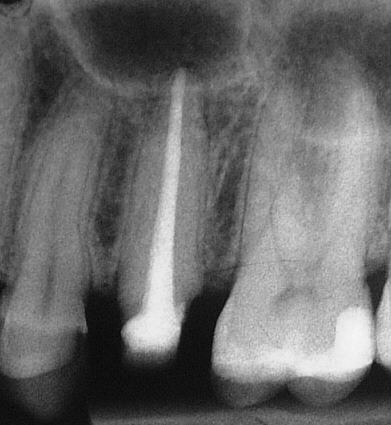

Devitaler, stark klopfempfindlicher 47 im November 2003,  der seit mehreren Wochen homöopathisch behandelt wurde (KLICK!)

Messaufnahme im Februar 2004. Leider haben wir die Fistel erst beim Spülen nach Überinstrumentierung bemerkt. Auf eine weitere Aufnahme zur Darstellung haben wir im Interesse der Patientin verzichtet (Klick!)